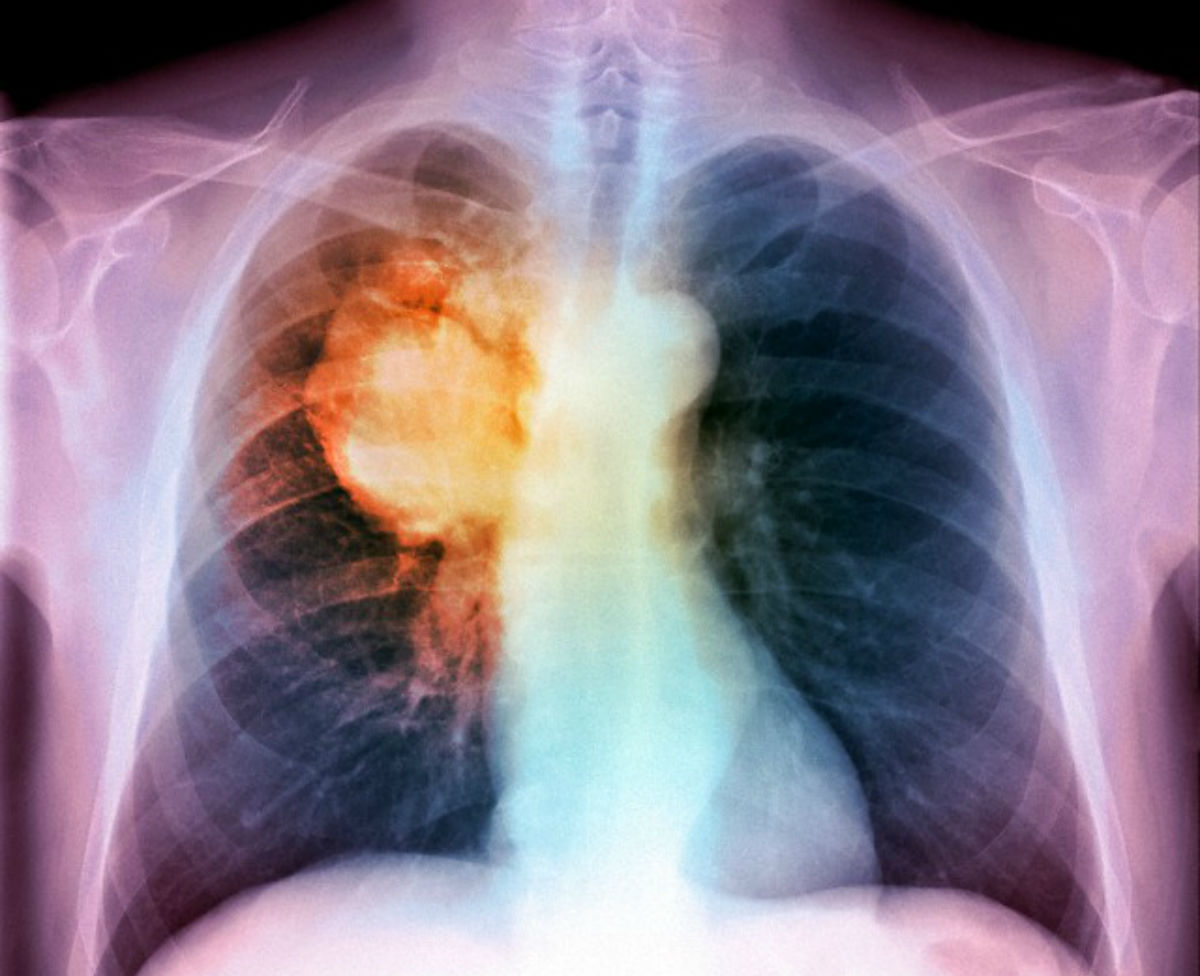

Il metodo, chiamato CancerSEEK è stato testato su oltre mille malati. Joshua Cohen, coordinatore del gruppo di ricerca, è riuscito a valutare le mutazioni di 16 geni tumorali, insieme ai livelli di 10 proteine circolanti nel sangue, per il cancro del seno, fegato, ovaie, polmone, stomaco, pancreas, esofago e colon retto. Il test è stato effettuato su 850 volontari sani e la restante parte su malati di tumori con diverse entità.